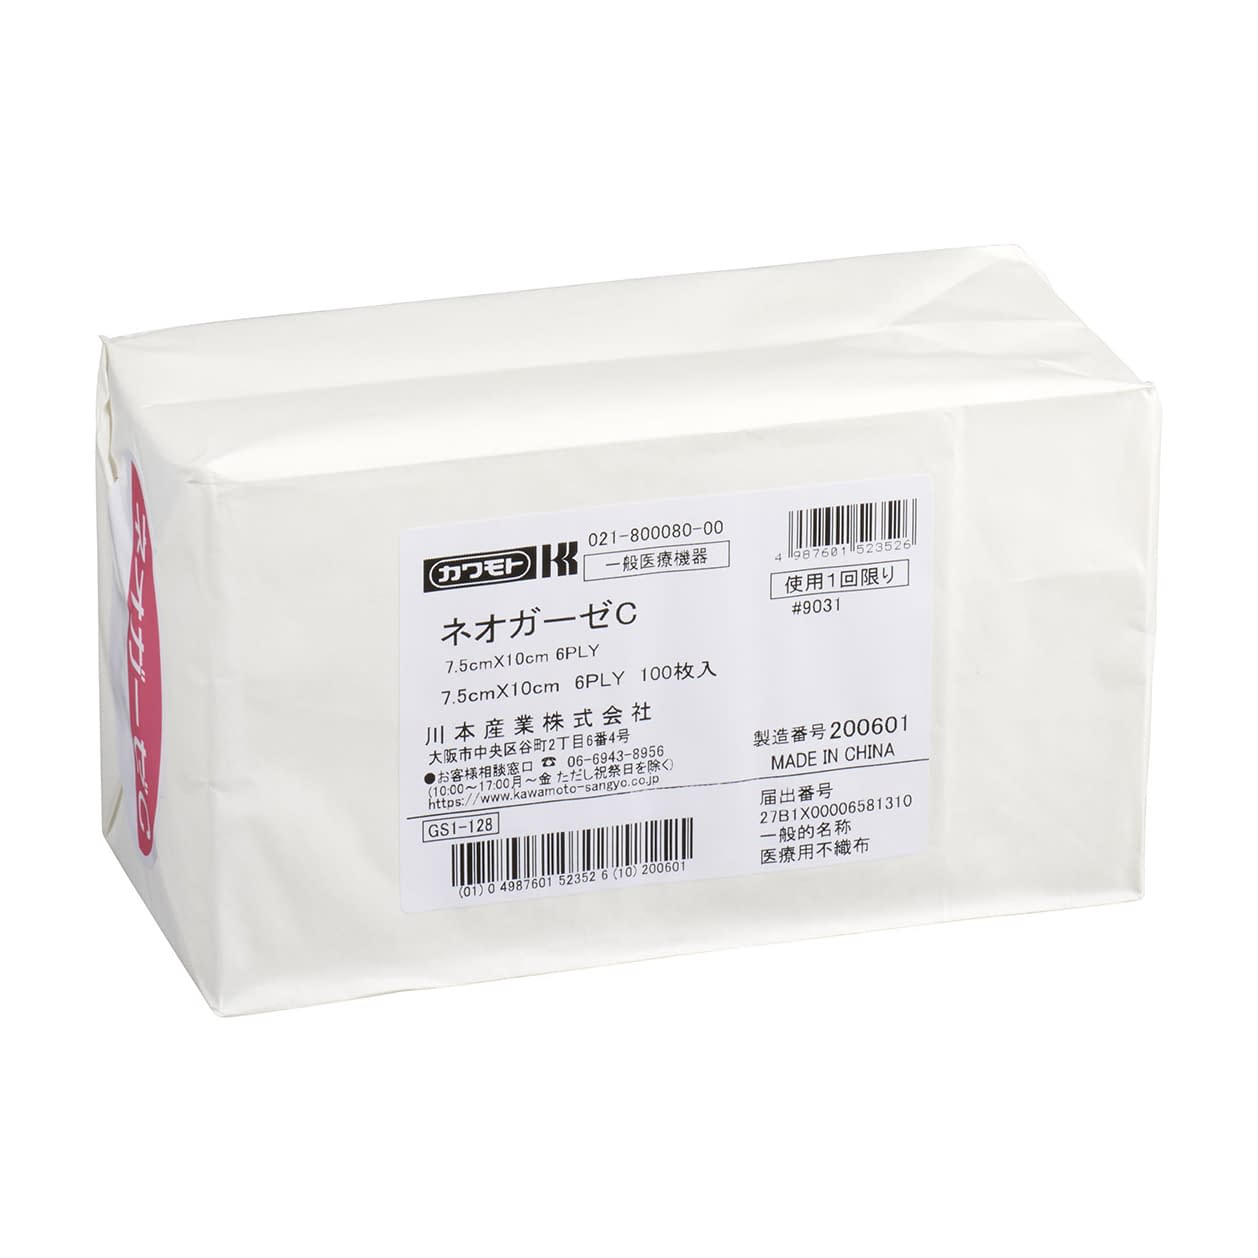

●純度の高い医療用の不織布ガーゼで、優れた吸水・保水性があります。●未滅菌(オートクレーブ・EOG滅菌可能)。

| 商品名 | (24-7612-02)未滅菌ネオガーゼC(6ply)7.5X10CM(100マイイリ) ミメッキンネオガーゼC(6PLY)(横井定)【1袋単位】【2019年カタログ商品】 |

| 商品コード | 24-7612-02 |

| 標準価格 | 1,000円(税抜き) |

| JANコード | 4987601523526 |

| メーカー | 川本産業 |